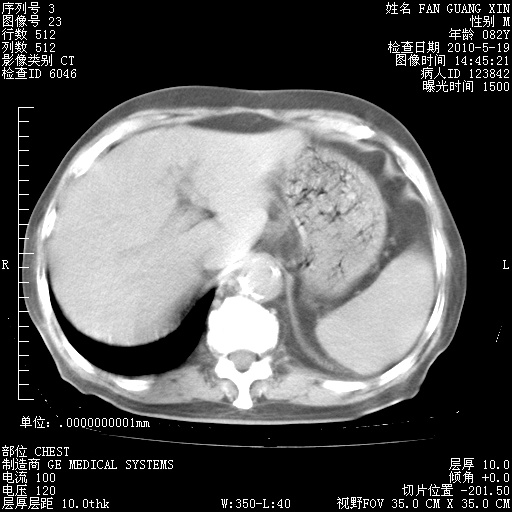

治疗3周后的肺部CT纵隔窗

从胸部影像学来看,的确有好转。至于目前为何发热不甚清楚?除了发热还有其他症状如有无喀痰,痰呈丝状吗?等等。尽量搜寻有无致发热其它可能原因?真菌?其它?如果的确无其他致发热的原因,考虑将甲强龙调至60-80mg bid/日。免疫全套基本无异常,考虑多系特发性肺间质纤维化